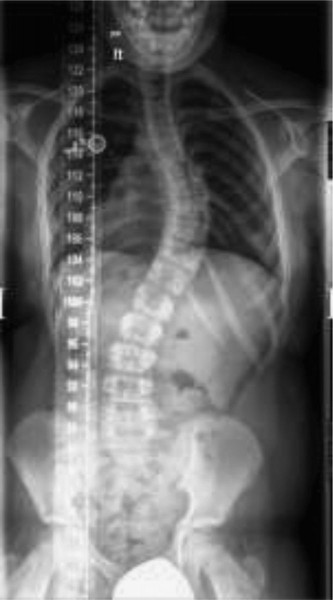

In room 1, you meet a girl who turned 10 years old 5 days ago. She has not yet started her menses. She is here with the chief complaint of “scoliosis.” She was recently seen by her pediatrician for a “well-child” visit, and as part of evaluation, a forward-bend test was performed that raised concern for a spine curvature. A PA full spine x-ray was performed (Fig. 10–18) and she was referred to you for evaluation.

Figure 10–18

After performing a physical examination in which there are no neurologic abnormalities detected, you measure her x-ray, and the curve measures 48 degrees. She is hyperkyphotic on the lateral x-ray. There is no spondylolysis or spondylolisthesis.

The correct answer is (E). This is a patient who just turned 10 years old this week and has a large scoliotic curve. This is clearly onset before the age of 10 in this premenarchal girl, therefore this is classified as juvenile scoliosis. It has been estimated that approximately 20% of children who have juvenile scoliosis (age of onset 3–10 years old) have an intraspinal anomaly; obtaining an MRI of the spine is important in their evaluation. You want to look for a Chiari malformation, syringomyelia (syrinx) and tethered cord, as well as less common findings such as a spinal cord tumor. In order to evaluate for those potential underlying diagnosis, the entire spine must be imaged and therefore choice E is the correct answer. “A” is not correct because, although a CBC may be desired before any potential surgical intervention, it is not needed now. The ANA and HLA-B27 are not needed in this case scenario. A bone density scan is also not a necessary part of the work-up of juvenile scoliosis. It can be obtained in selected patients for whom there is concern about underlying bone density. Bracing for a curve of this magnitude is not likely to be effective. Even if the curve were smaller and bracing was a consideration, you would still get an MRI for this child. “D” is not correct because in order to thoroughly evaluate for potential problems with the neural axis, you need base of brain/cervical spine imaging to evaluate for Chiari malformation, as this patient has.